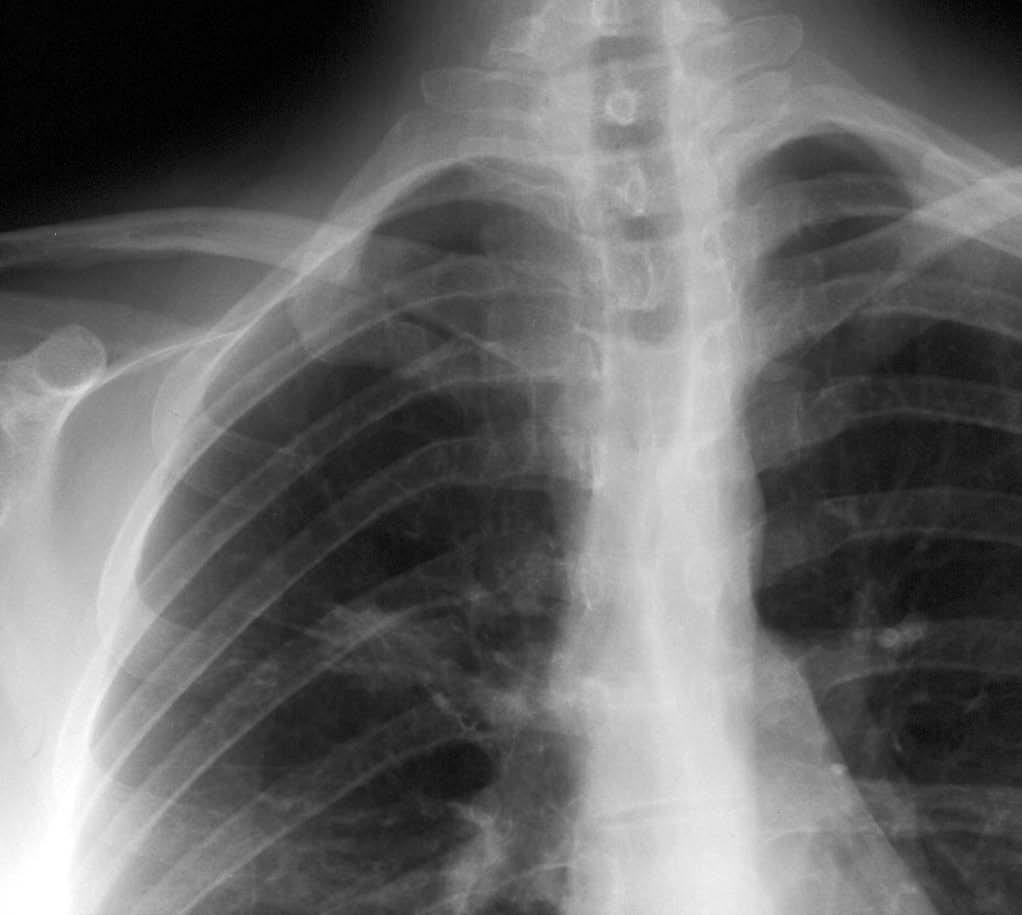

Mujer de 26 años de edad, fumadora de 10 cigarrillos al día, sin otros antecedentes de interés, que consulta por dolor torácico pleurítico sin fiebre, ni otra sintomatología acompañante. Las pruebas de laboratorio fueron normales. En la radiografía de tórax se observó una lesión redondeada de unos 3 cm en el lóbulo superior derecho, parahiliar (fig. 1). Ante la posibilidad de que se tratara de una neumonía redonda, recibió tratamiento antibiótico empírico con amoxicilina-clavulánico, sin cambios radiológicos. Se realizó una tomografía computarizada (TC) torácica sin contraste intravenoso, que mostró un nódulo pulmonar de bordes mal delimitados de 2 x 3 cm en el segmento anterior del lóbulo superior derecho, con tres nódulos satélites adyacentes (figs. 2 y 3). La fibrobroncoscopia fue normal. La citología del broncoaspirado y cepillado bronquial fue negativa para malignidad. Los cultivos para bacterias, hongos y micobacterias resultaron estériles. Se practicó una punción aspiración con aguja fina (PAAF) transtorácica bajo control con TC, obteniéndose material sin evidencia de malignidad. Ante la ausencia de diagnóstico y la imposibilidad para descartar malignidad se realizó una lobectomía superior derecha.

Fig. 1.--Detalle ampliado de radiografía de tórax póstero-anterior en la que se visualiza un nódulo de contornos mal definidos en el lóbulo superior derecho.